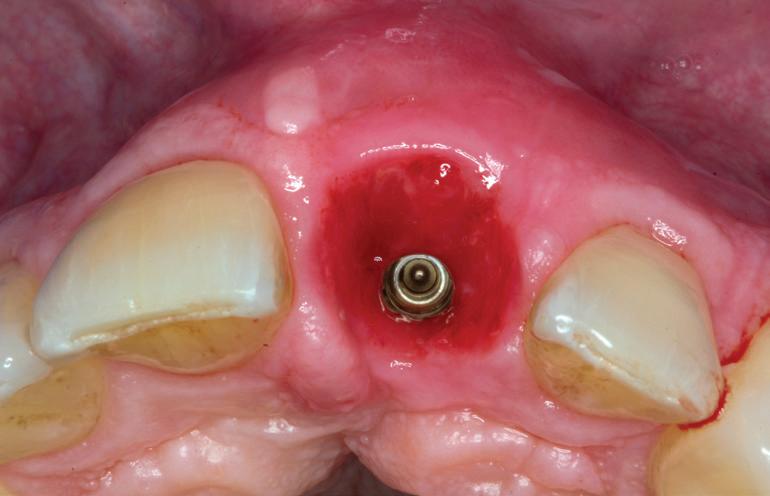

RECONSTITUIREA țesuturilor moi periimplantare. Scopul acestui raport de caz este de a demonstra procedurile chirurgicale utilizate pentru corectarea unui defect al țesuturilor moi periimplantare folosind țesutul moale interdentar în combinație cu tuberozitatea ca locație donatoare de țesut conjunctiv, utilizând o abordare prin tunelizare într-o zonă estetică.

Până la 40% dintre pacienții cu implanturi pot fi afectați de periimplantită după cel puțin 1 an de funcționare. Cel mai bine este ca defectele periimplantare să fie abordate în stadiile incipiente, deoarece cu cât defectul este mai mare, cu atât este mai dificil de tratat. Implanturile dentare trebuie evaluate ca parte a examenului anual al pacientului. Odată detectată BOP, diagnosticul este de mucozită periimplantară impunându-se o serie de recomandări pacientului cu privire la modul de corectare a inflamației, fie prin îmbunătățirea îngrijirii la domiciliu, îndepărtarea biofilmului bacterian și/sau terapia cu laser.

De asemenea, trebuie evaluate anual modificările radiografice. În ședința de inserție a restaurării, se înregistrează o radiografie bitewing standardizată pentru a permite evaluarea anuală a modificărilor osoase din jurul implantului. Remodelarea osului alveolar în primul an este bine documentată și depinde de tipul de implant utilizat; cu toate acestea, nu ar trebui să apară apical de primul filet al implantului. Prin urmare, este importantă abilitatea de a vizualiza filetele implantului pe radiografii. Modificările pierderii osoase de 2 mm sau mai mult după primul an reprezintă un semn de periimplantită. De îndată ce pierderea osoasă este recunoscută, pacientului trebuie să i se recomande terapia imediată pentru a opri procesul de boală.